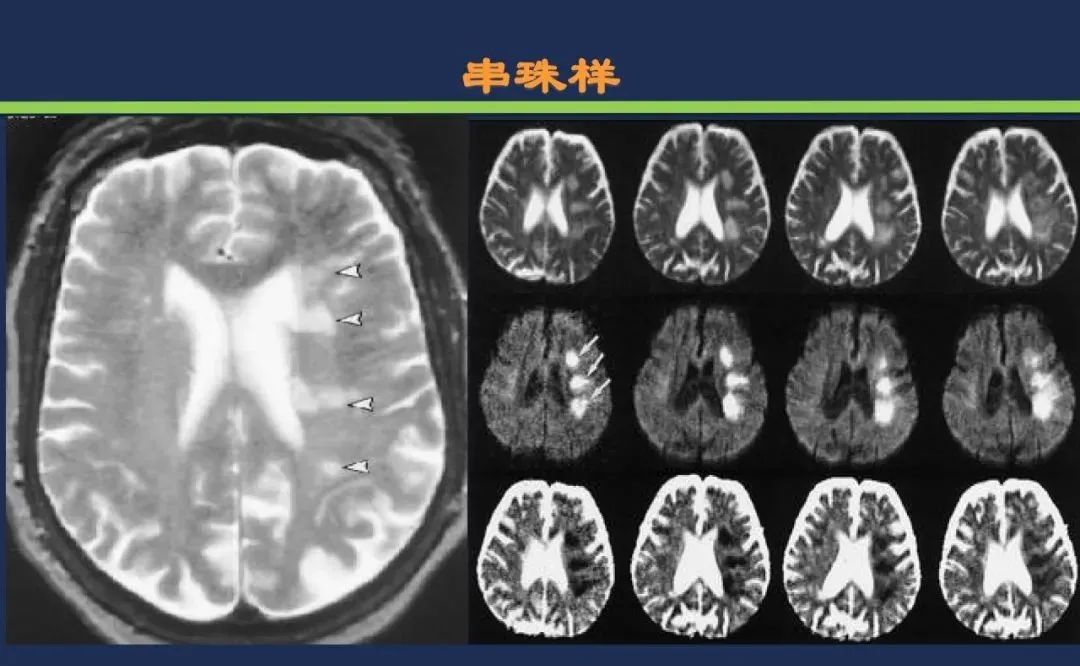

从梗死部位推测责任血管

颈内动脉系统梗死颈内动脉大脑中动脉

分水岭梗死皮质前型+皮质后型+后上型皮质下前型+皮质下后型+皮质下上型+皮质下外型+皮质下下型